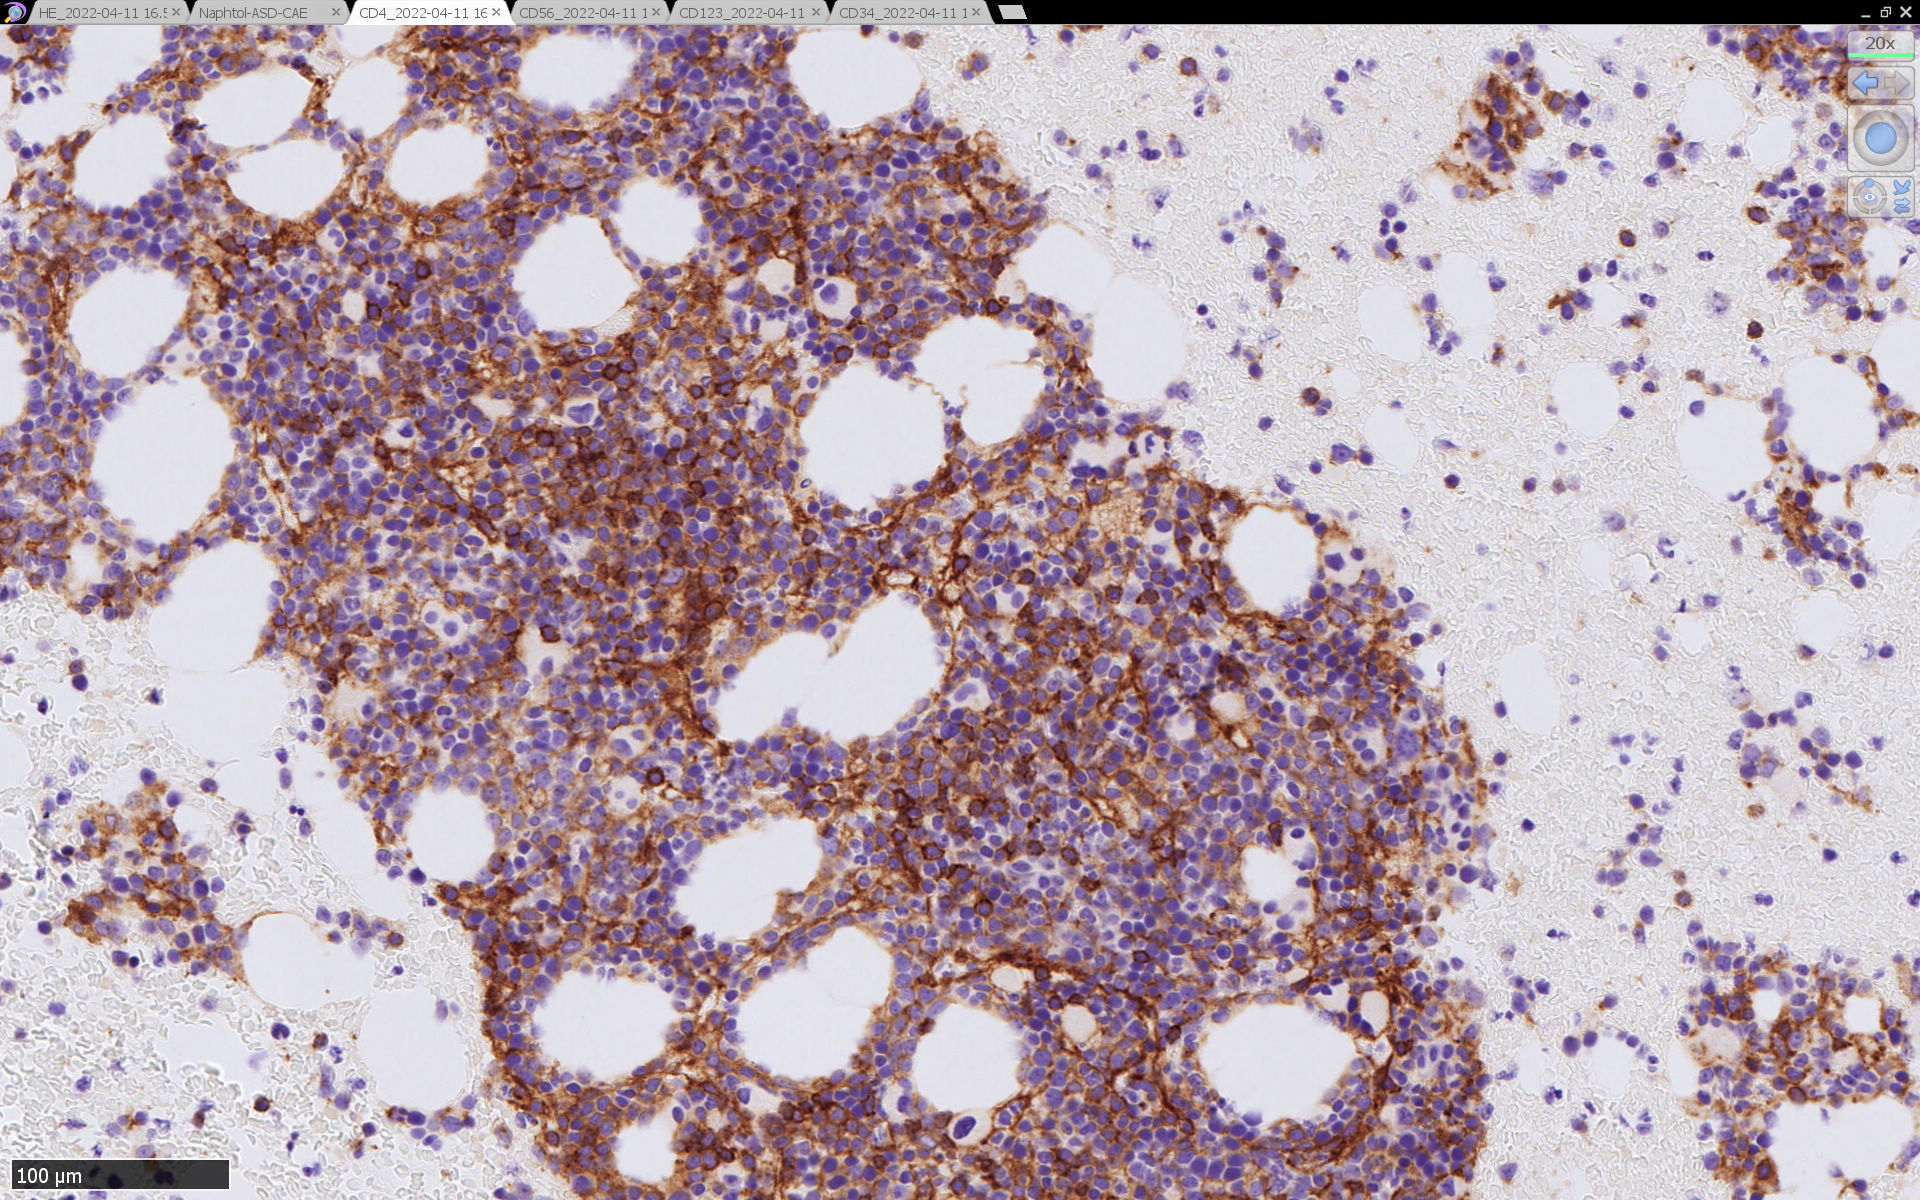

免疫染色

CD4は染まりすぎの感がある(濃く染まる細胞はCD4+ T-cellかもしれない). CD56, CD123が陽性で可能性が高くなり, BPDCNの診断にはCD34は陰性であることが必要

TCF4、CD123、TCL1をconsultationにより染色していただき, 陽性を確認した. CD34-, lysozyme-, CD123(おいてある病院は少ないかも)をしらべて, BPDCN研究会あてconsultationをする流れでしょうか.